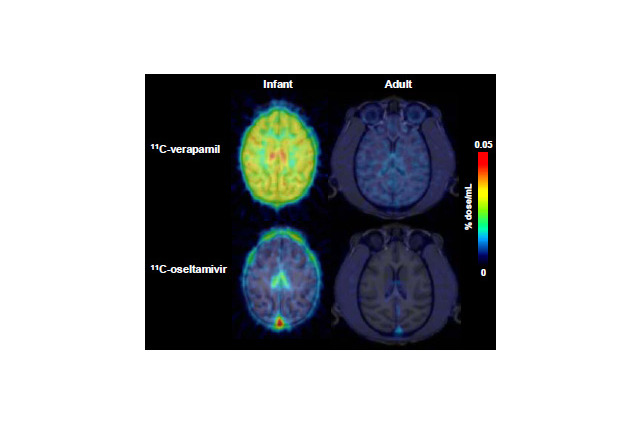

子どもの脳はタミフルの影響を受けやすい…理研ら確認